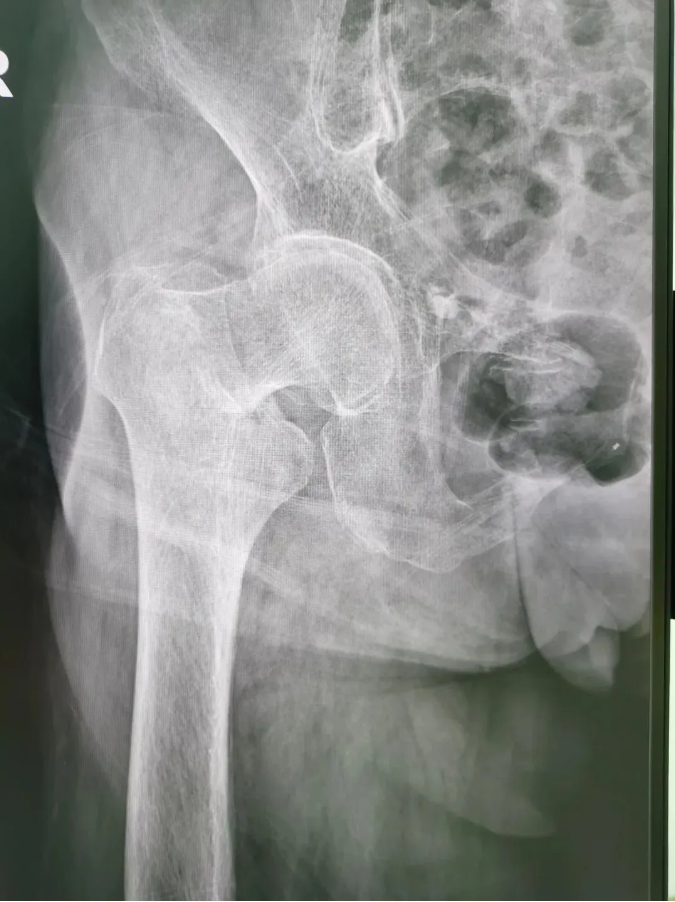

今年91歲的陳婆婆,9月份時在家不慎摔倒,右臀部著地,當下感到髖部劇烈疼痛并活動受限。為求進一步治療,到順德和平外科醫(yī)院骨三區(qū)就診,該區(qū)主任楊升平主任為其診療,被診斷為“右股骨頸骨折”,需進行右股骨頸骨折經(jīng)皮閉合復(fù)位空心螺釘內(nèi)固定手術(shù)。

術(shù)前X光

陳婆婆91歲的高齡,有高血壓和冠心病病史,通過傳統(tǒng)開刀手術(shù)治療風險較大。經(jīng)骨三區(qū)專業(yè)醫(yī)療團隊討論,決定讓天璣?骨科機器人上場,輔助完成微創(chuàng)手術(shù)。